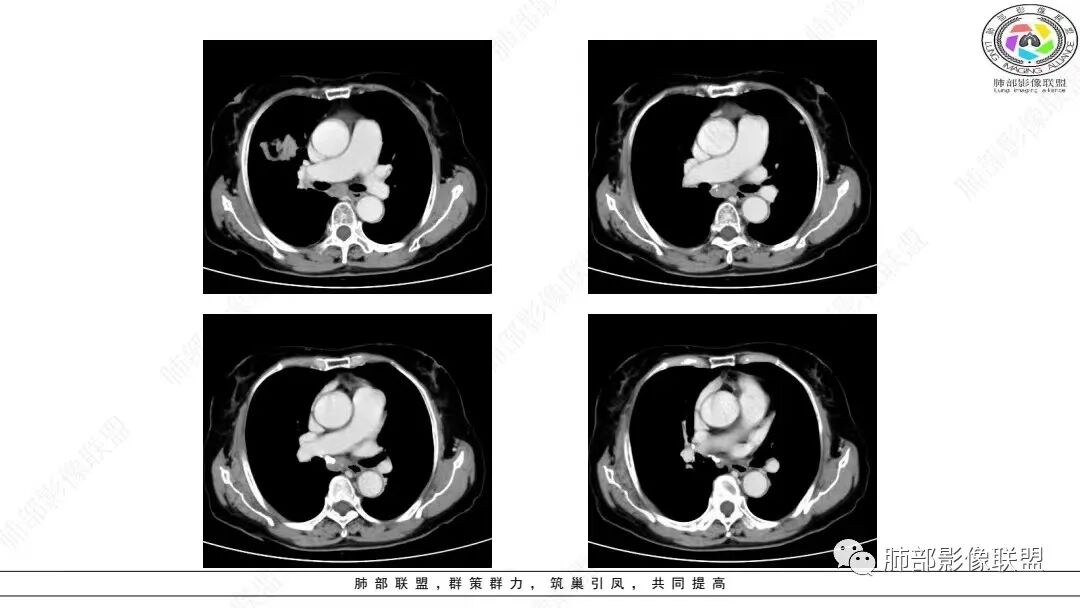

2.影像学特点:右肺上叶前段胸膜下不规则较大团块影,边界清楚欠光整,浅分叶,肺血管支气管出入,边缘膨隆胸膜凹陷具有一定张力,未见典型粗短毛刺,部分围以边界清楚的磨玻璃影,灶周小叶间隔增厚。块影密度不均,渐进性强化,可见砂砾样钙化,未见明显液化坏死或空洞。增强后病灶显示渐进性强化。MIP显示病灶内肺动脉穿行、并部分肺动脉受侵变细。纵隔及右锁骨上(胸廓入口)见肿大淋巴结。两肺可见多发大小不一的结节影,边界清楚,随机分布。

本组大部分病灶(64.75%)CT平扫密度均匀;增强后多数病灶以中度(71.75%)、渐进性强化(75.13%)为主,动脉期病灶内常见异常细小杂乱血管影(55.96%)。    笔者据此认为密度均匀且不易出现坏死、呈中度渐进性延时强化为肺LELC的特点,可能与病灶内部含有丰富的淋巴细胞浸润和大量纤维组织增生及胶质有关;病灶内部分细小杂乱血管影可追踪为支气管动脉,推测可能为新生肿瘤血管,提示肿瘤血供丰富,不易出现坏死;但新生肿瘤血管通常不成熟,血管通透性增高,致使对比剂外渗,使肿瘤表现为延迟强化。肺LELC生长较快时,由于血供不足,也可出现液化坏死及钙化等改变。肺LELC密度均匀、液化坏死较少及延迟强化,可作为其与肺鳞癌或腺癌的鉴别要点。

多数学者认为血管支气管包埋征是肺LELC的特征性表现。本组41.97 0A(81/193)病灶内部动脉期见血管包埋征,而血管形态正常,无明显受侵、狭窄,与上述研究报道相符,可能提示肺LELC具有类似淋巴瘤相似的特点,即易浸润周围结构,引起间质增厚、肺泡壁破坏及肺泡腔充盈,但较少侵犯血管[1 3|。但本组108例(108/193,55.96%)表现为血管受侵、狭窄,75.82%支气管受累狭窄闭塞,可能提示肺LELC病灶内血管受侵狭窄及支气管破坏较淋巴瘤更多见[1 3|,较大肺LELC病灶更易出现血管、支气管受侵、破坏。

综上所述,右肺中叶、两肺下叶纵隔胸膜旁肿块,边界清、浅分叶、淋巴结肿大,伴有类胸膜尾征、增强动脉期血管包埋征、周围肺区磨玻璃密度影及网格增粗影是肺LELC相对特征的CT表现,但最终诊断仍须依赖组织病理学和免疫组织化学染色结果。